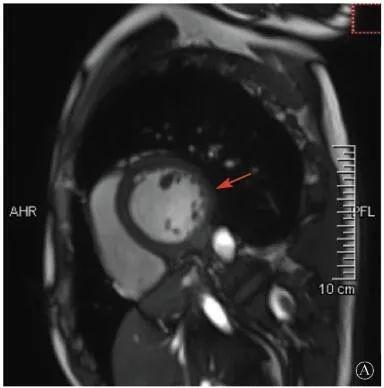

案例介紹:患者男性,20歲,因為"胸痛4個月,加重1月余"于2019年7月10日入院?;颊?019年4月無明顯誘因出現(xiàn)心前區(qū)隱痛,VAS 3分,無放射,無胸悶、憋氣、活動后氣短,每月發(fā)作1~2次,未在意。同年5月體檢發(fā)現(xiàn),肌酸激酶(CK)2928 U/L、肌酸激酶MB質(zhì)量(CK-MB)46 U/L、心肌肌鈣蛋白I(cTnI)0.055 ng/ml。6月初,患者"感冒"后出現(xiàn)心前區(qū)疼痛加重,為過電樣疼痛,VAS 5分,無放射,持續(xù)約30~60 min可好轉(zhuǎn),胸痛每周約發(fā)作2次,否認呼吸困難、胸悶、心悸,否認活動耐量下降。6月8日,患者就診于外院查血生化:CK 1 215→1433 U/L,CK-MB 47 U/L,cTnI 30.17→31.79 ng/L;血脂(-);抗核抗體譜(-);超聲心動圖:左室增大,左室舒張末內(nèi)徑57 mm,左室射血分數(shù)39%,輕度二尖瓣關(guān)閉不全;磁共振心肌灌注延遲動態(tài)成像(圖1):左室稍增大,收縮功能稍減低;基底部至心尖部左室下壁及側(cè)壁、心尖部左室前壁心外膜下心肌纖維化,考慮非缺血性心肌病;肌電圖:肌源性損害(偏慢性)。診斷"多發(fā)性肌炎、心肌損傷",予患者倍他樂克緩釋片23.75 mg/d、培哚普利0.5 mg/d、螺內(nèi)酯20 mg/d口服,患者未再出現(xiàn)心前區(qū)疼痛,但步行1 km左右會出現(xiàn)氣短、乏力。為進一步明確心力衰竭病因收入我院?;颊呱细咧衅鸪霈F(xiàn)體育課等劇烈活動后雙下肢明顯乏力,不能耐受1 km長跑類運動,日常體力活動不受影響,否認肌肉酸痛等不適。此次發(fā)病以來,一般情況尚可,否認尿量減少,體重無明顯變化。既往史:否認高血壓、冠心病、糖尿病病史。個人史:否認特殊毒物藥物接觸史,無煙酒嗜好。婚育史、家族史:未婚未育,否認家族類似病史,否認遺傳病史。入院查體:脈搏69次/min,血壓112/70 mmHg,指氧(自然狀態(tài))98%,體質(zhì)指數(shù)21.1 kg/m2;無皮疹;雙肺呼吸音清;心律齊,未聞及雜音;肝脾不大;雙側(cè)腓腸肌肥大,肌肉無壓痛;四肢肌力Ⅴ級、肌張力正常。雙下肢不腫。輔助檢查:入室床旁超聲心動圖提示左室壁運動普遍減低,心尖部、左室下后壁為著,肌小梁增多。

左室壁較廣泛心外膜下延遲強化,可見左室下后壁肌小梁增多(箭頭所示)

圖1 患者外院磁共振心肌灌注延遲動態(tài)成像